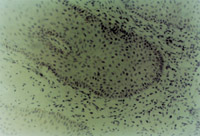

MEBT治療20天,深度創(chuàng)面處組織切片可見新生較完整的復層鱗狀上皮組織,表皮層細胞形態(tài)已經(jīng)趨于正常,真皮層膠原纖維細胞和微血管形態(tài)已經(jīng)出現(xiàn)。

治療30天后,創(chuàng)面上皮組織再生修復良好(圖5-3-5),皮膚結構已經(jīng)基本正常(圖5-3-6)。

5-3-6 治療30天后的創(chuàng)面其表皮組織,真皮組織結構已呈生理狀態(tài)  HE×20